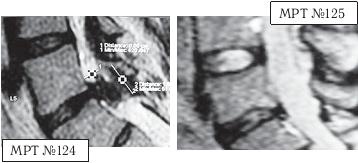

На МРТ № 128 наблюдается состояние поясничного отдела позвоночника после операции: рецидив грыжи межпозвонкового диска в сегменте LV-Sr с отрывом секвестра и его миграции в краниально-дорсальном направлении, разрыв задней продольной связки. На МРТ № 129 наблюдается состояние поясничного отдела позвоночника после лечения методом вертеброревитологии: отсутствие грыжи межпозвонкового диска в сегменте L — S. В межпозвонковых дисках в сегментах LIV-LV, L — SI наблюдается процесс репаративной регенерации. ![]() На МРТ № 130 наблюдается состояние поясничного отдела позвоночника после двух хирургических операций: рецидив грыжи межпозвонкового диска в сегменте LV-SI. На МРТ № 131 наблюдается состояние поясничного отдела позвоночника после лечения методом вертеброревитологии. Рецидив грыжи межпозвонкового диска после двух хирургических операций — и это у молодого человека в возрасте 16 лет! Чрезмерное увлечение компьютером, малоподвижный образ жизни основательно подорвали его здоровье. Всё это привело к тому, что в течение года, начиная с пятнадцатилетнего возраста, он практически не выходил из больниц. После первой хирургической операции на позвоночнике, менее чем через месяц, боли возобновились. Спустя два месяца его вновь прооперировали по поводу рецидива — грыжи межпозвонкового диска. После второй хирургической операции боли наблюдались практически два месяца подряд, потом затихли, но полностью так и не прошли. Через пять месяцев появилась слабость в обеих ногах. Сделали снимки МРТ, диагностировали рецидив грыжи межпозвонкового диска, естественно рекомендовали сделать очередную третью хирургическую операцию. В промежутках между операциями молодой пациент несколько раз находился на стационарном лечении в неврологическом отделении городской больницы. Именно там, после того как у парня была диагностирована очередная грыжа, лечащий врач посоветовал не спешить с третьей операцией и порекомендовал ему обратиться ко мне в клинику. Конечно, этот случай был далеко не простым и пришлось основательно потрудиться как мне, так и самому пациенту над восстановлением его здоровья. Но зато результат порадовал всех тех, кто непосредственно участвовал в этом процессе, и кто косвенно ему способствовал. Можно сказать, ещё одна судьба была изменена и молодой человек спасён от инвалидной коляски. МРТ № 132МРТ № 133 ![]() На МРТ № 132 и МРТ № 133 — увеличенные фрагменты МРТ № 130 межпозвонковых дисков в сегментах LIV-LV и LV—SI до лечения методом вертеброревитологии. Структура межпозвонковых дисков неоднородна. ![]() На МРТ № 134 и МРТ № 135 — увеличенные фрагменты МРТ № 131 межпозвонковых дисков в сегментах LIV-LV и LV—SI, после лечения методом вертеброревитологии. Наблюдается весьма интересное явление — репаративная регенерация. Обратите внимание, насколько уменьшилось количество некрозной (мёртвой) ткани и увеличилось функциональной (живой) ткани. Примечательно, что хондроциты при регенерации в данной фазе формируют вертикальные и наклонные «колонны» согласно вектору нагрузки на межпозвонковый диск в районе фиброзного кольца. В центре межпозвонкового диска наблюдается не менее интересное явление — начало регенерации пульпозного ядра! Следующий случай можно назвать абсолютно беспрецедентным в истории науки вертебрологии и новым этапом в развитии вертеброревитологии. С помощью метода вертеброревитологии удалось практически полностью восстановить (по сути заново вырастить) отсутствующий межпозвонковый диск! И это без всяких химических препаратов, а исключительно благодаря естественному восстановлению биомеханики позвоночника — выстраиванию определённой биомеханической конструкции. При построении последней были достигнуты оптимальные условия для активизации резервных возможностей организма, что, в свою очередь, способствовало запуску репаративной регенерации вплоть до реституции диска, который в своё время был практически полностью удалён. Это удивительное явление, сравнимое разве что с реанимацией. Впрочем, всё по порядку. |